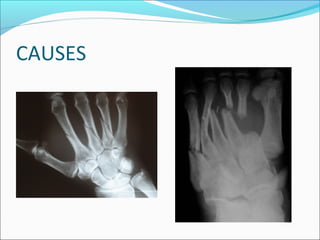

Causes

 Fracture of a long bone

(Supracondylar humerus,

forearm, hand,tibia and

foot)